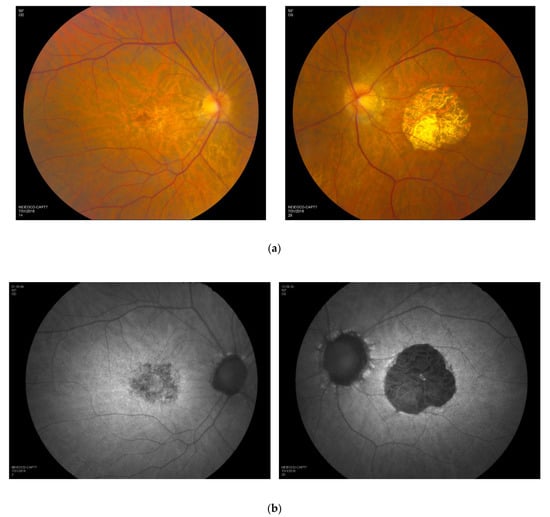

3.5. Retinal Imaging

3.6. Longitudinal Data